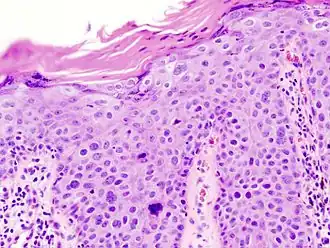

Invasive disease

In invasive cSCC, tumor cells infiltrate through the basement membrane. The infiltrate can be somewhat difficult to detect in the early stages of invasion: however, additional indicators such as full-thickness epidermal atypia and the involvement of hair follicles can be used to facilitate the diagnosis. Later stages of invasion are characterized by the formation of nests of atypical tumor cells in the dermis, often with a corresponding inflammatory infiltrate.[12]

Superficially invasive cutaneous squamous-cell carcinoma. These lesions often do not show the marked pleomorphism and atypical nuclei of cSCC in situ, but manifest early keratinocyte invasion of the dermis.[12] -

High magnification demonstrates the pleomorphism of the invading keratinocytes[12] -